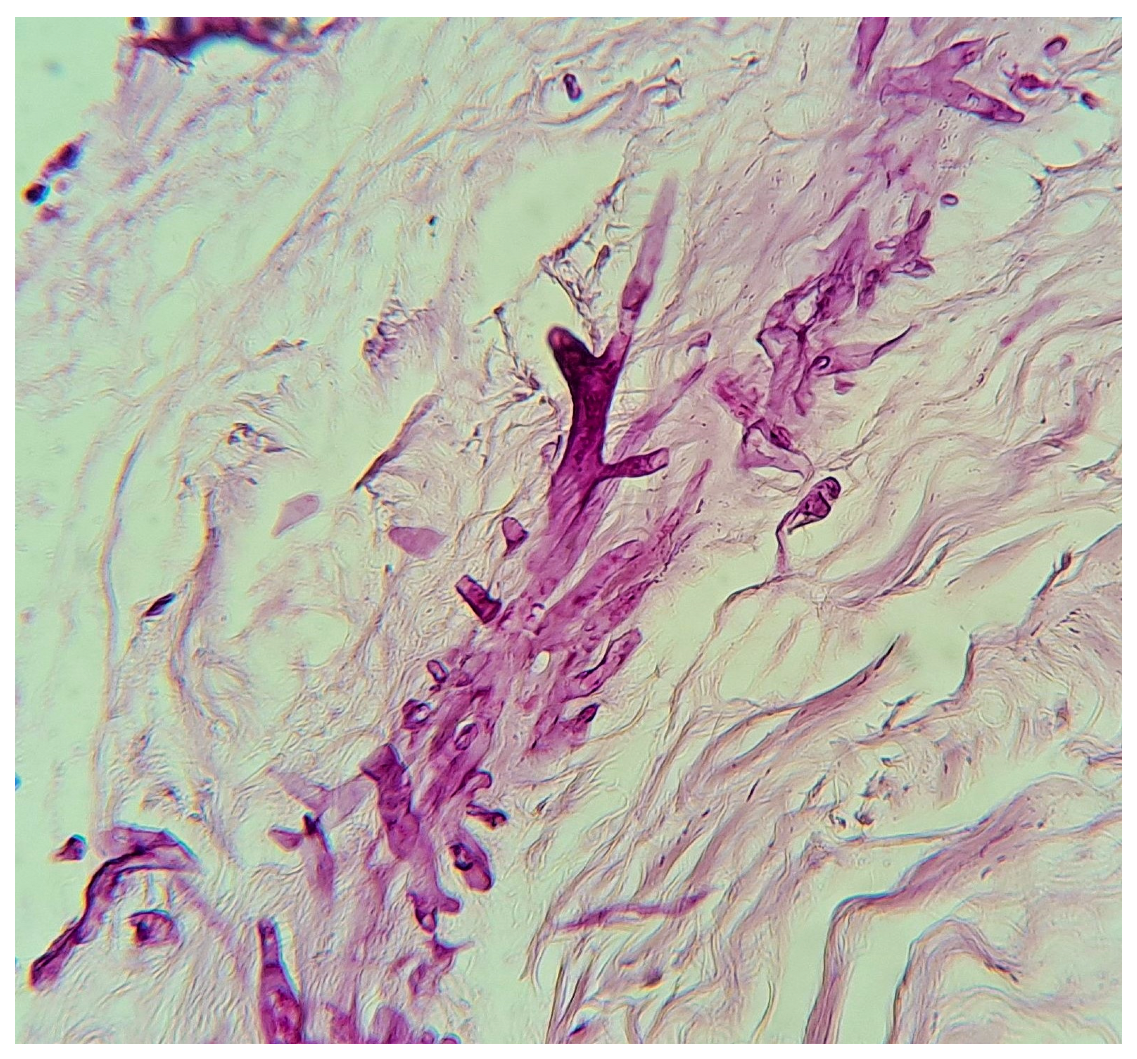

The diagnosis of mucormycosis in neonates was significantly delayed due to the nonspecific nature of the initial symptoms and their similarity to other clinical entities, particularly NEC in its gastrointestinal variant. In 98.3% of cases, the diagnosis was confirmed through histopathology or culture (Figure 8), highlighting the importance of early biopsies in high-risk patients and surgical intervention in gastrointestinal cases. The use of molecular biology techniques was not reported.

Figure 8.

Biopsy of a mucormycosis case, PAS stain, 40×, courtesy of Roberto Arenas.